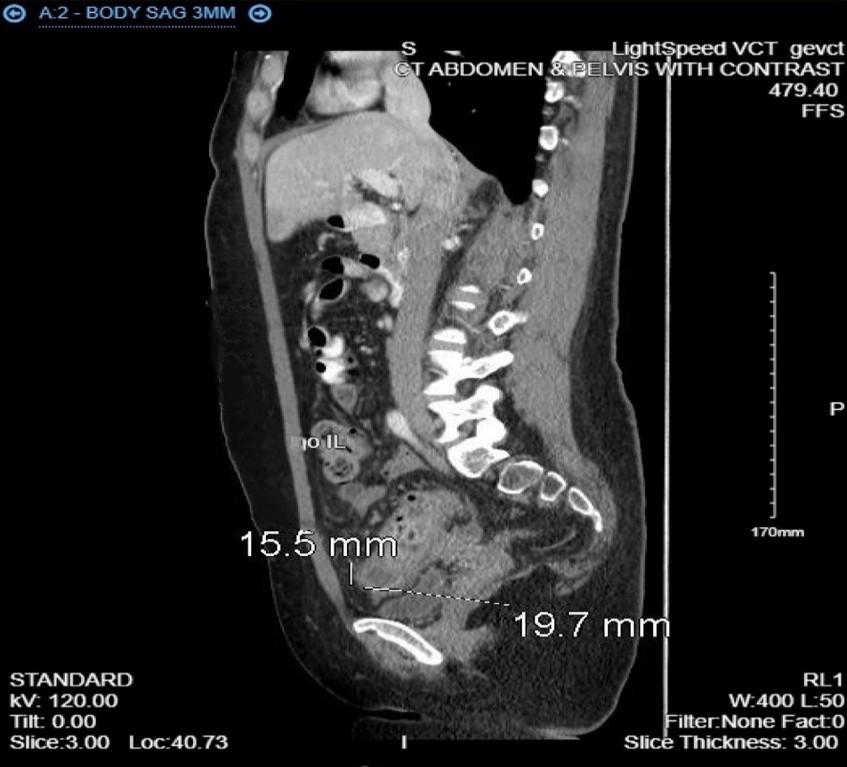

CT imaging showed sigmoid colon wall thickening, a 2.0 × 1.6 × 1.0 cm intramural abscess, and free adnexal fluid, raising suspicion for colitis or inflammatory bowel disease with possible gynecologic etiology.

A 35-year-old woman with a history of dysmenorrhea and chronic constipation presented with acute abdominal pain to ED . Her symptoms on presentation diffuse abdominal pain, nausea, vomiting, diarrhea, chills, and bright red blood per rectum. She had a history of alpha thalassemia, dysmenorrhea fo that she was initially on NuvaRing since 2018, later switching to ParagardIUD placed 2024. Patient was complaining for consitpaiton with mild relief from magnesium citrate and prune juice and other OTC medications.  A CT scan of abodmen with conatrast revealed sigmoid colonic wall thickening with small intramural abscess measuring up to 2.0 x 1.6 x1.0 cm., concerning for colitis of infectious or inflammatory origin and  adnexal free fluid, raising the possibility of gynecological pathology. CBC remarkable for mildly low white count of 13.4, CMP was normal.

Fig. 2 Abdominal computed tomography showed irregularly enhanced wall thickening of mass in the sigmoid colon (white-black arrow). Sagital view